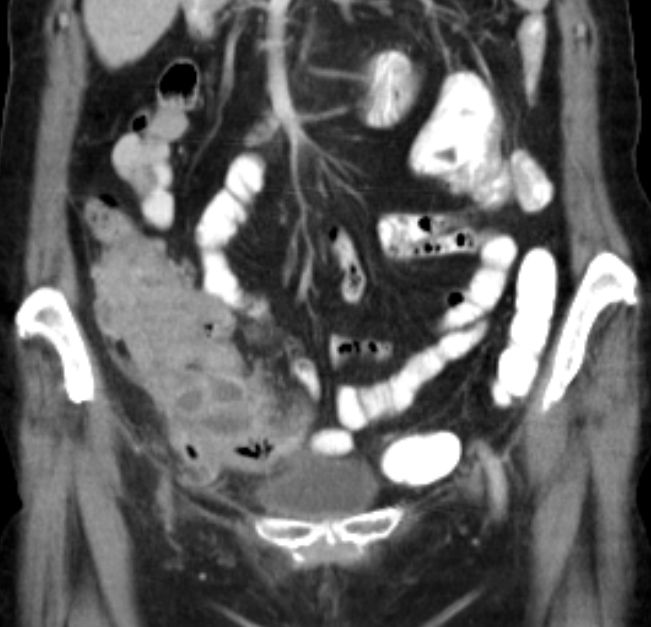

66-jährige Frau mit einem Appendixtumor. Histologisch niedrig maligne muzinöse Neoplasie.![]() |

![]() |